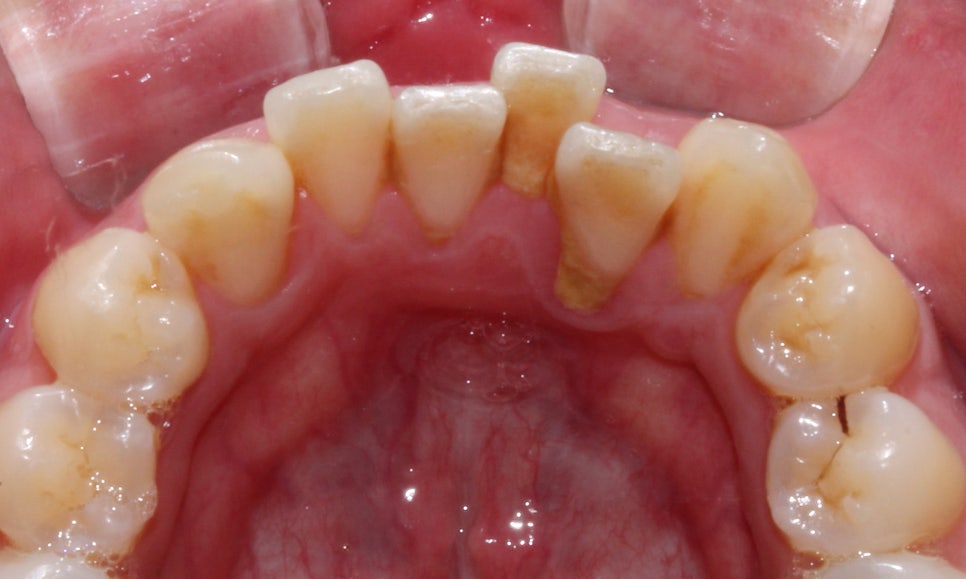

총생으로 들쭉날쭉하게 배열되었던

아랫니 역시 교정 후 치열이 가지런하고

바르게 교정된 모습입니다!

부분 교정에 사용되고 있으며 환자분께서는

상하악 전치부만 2D교정을 진행하셨습니다!

이 점 유의하여 포스팅을 읽어주세요^^